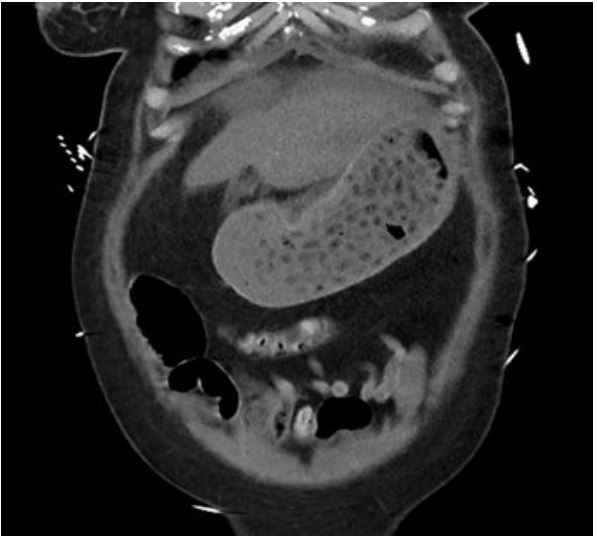

New Zealand National Poison Centre was consulted 30 hours after her initial presentation. The ingested dose of 309 mg/kg of venlafaxine and 224 mg/kg of lamotrigine significantly exceeded the intervention threshold, (12.5 mg/kg and 30 mg/kg for venlafaxine and lamotrigine, respectively) [7,8]. Abdominal cross-sectional imaging and/or urgent gastroscopy was recommended to assess/remove any remaining pill burden. Abdominal Computed Tomography (CT) 36 hours after the initial presentation revealed large pill concretion within gastric lumen (Figure 1). Urgent gastroscopy using therapeutic endoscope (GIF-2TH180, dual channel 3.7 mm and 2.8 mm diameter, Olympus Medical, Japan), found a large conglomerate of tablets in the stomach (Figure 2). Pill retrieval was attempted with a retrieval basket (Meditalia® 30x60 mm Loop Net, Italy) and a polypectomy snare (SnareMaster Plus, 10 mm, Olympus Medical, Japan). The procedure was technically challenging due to the large, compact nature of the concreted pharmacobezoar. The pharmacobezoar could not be easily broken down or removed and significant amount of pill burden remained. A last resort laparotomy was then contemplated to aid gastric decontamination, but the patient was deemed hemodynamically too unstable. She continued to deteriorate despite all available supportive measures and died a few hours later

Figure 1: Coronal view of the abdominal computed tomography in Case 1, revealing a large number of pills within the gastric lumen, with the appearance of a pill concretion.